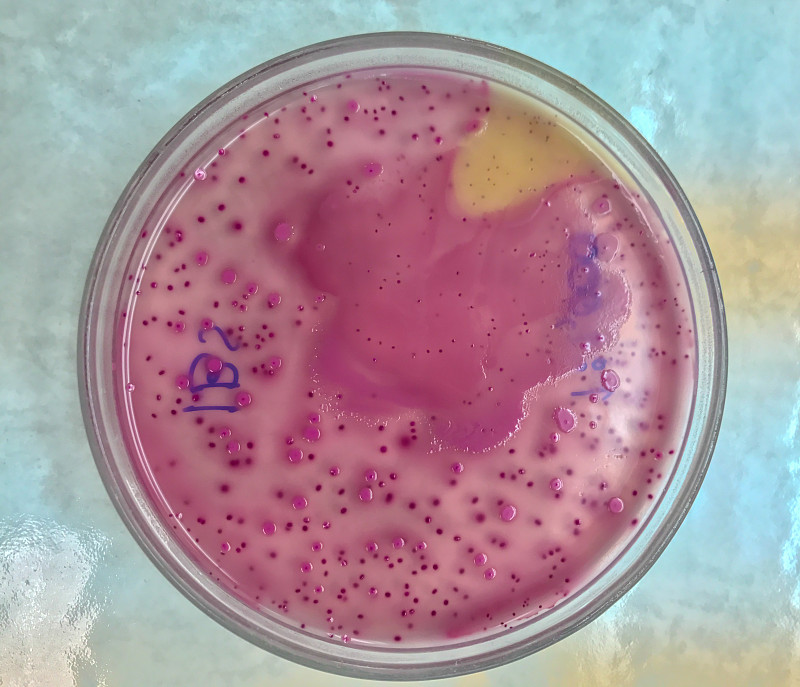

培养基板上的细菌菌落详情

细菌菌落详情

细菌菌落详情

细菌培养详情